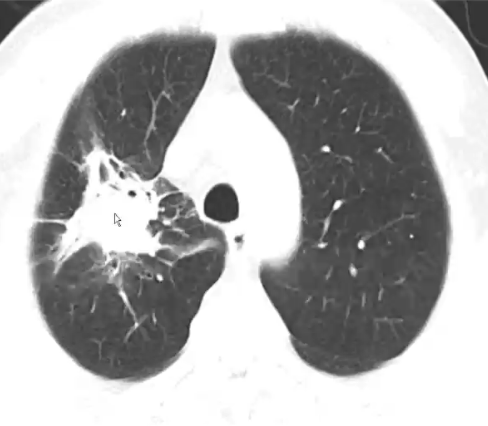

❖ 血管侵袭:大结节(>1cm)(菌丝累及小动脉),肿块样实变、梗死样实变(菌丝累及中等动脉),晕征

❖ 气道侵袭:簇状小叶中心结节、支气管周围实变、磨玻璃密度影、光滑的支气管壁增厚

❖ 坏死性肺炎:空气新月征、空洞、低密度征、反晕征、鸟巢征